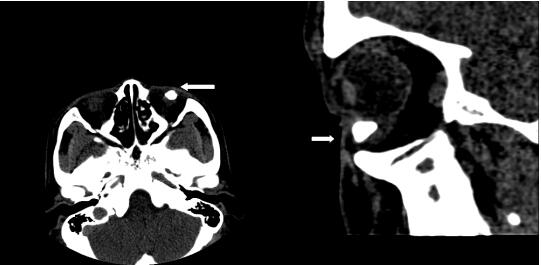

西安凤城医院眼科近日收治了一位48岁的中年男子,既往27年前左眼被炮炸伤,当时大量砂石击入颜面部,因医疗环境较差,未予系统治疗,27年来,左眼几乎无视力,且常有分泌物溢出,眼球转动障碍。胡铁明主任仔细查体发现:左眼视力为指数/10cm,下睑可触及一直径约10mm大小的肿块,活动度差,与球壁相连,挤压可见少许分泌物溢出,下睑可见一扇形组织自下穹窿部粘连于6点位角膜缘,眼球向上转动受限,瞳孔呈竖状梭形,直径约1mm,对光反射迟钝,晶状体混浊,玻璃体及眼底窥不清。眼眶CT检查示左侧眶内三角形致密影,考虑异物滞留可能。(如图CT箭头指示)